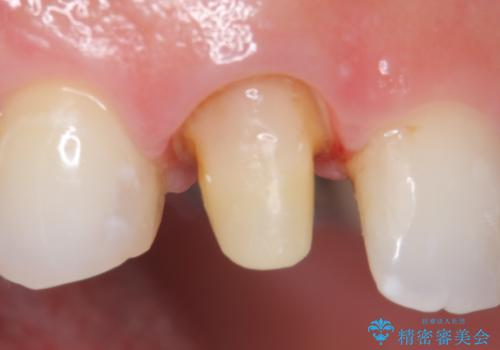

- 数年前に右上3の根管治療を行ったが、段々と色が気になってきたので、セラミックによる治療を行いたいといらっしゃった方の症例です。

再根管治療終了後、オールセラミッククラウンによる補綴を行いました。